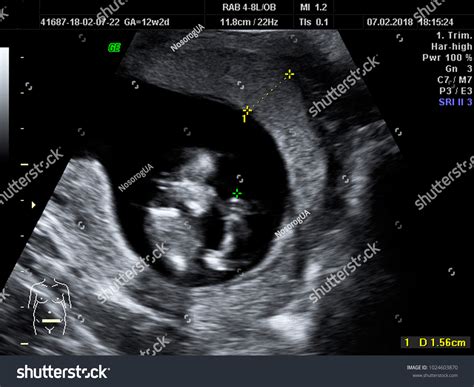

Pregnancy is an exciting journey filled with milestones, and one of the most anticipated moments is the 12 week sonogram. This ultrasound scan, typically performed between 11 and 13 weeks of pregnancy, offers a wealth of information about the developing fetus and the mother's health. Understanding what to expect during a 12 week sonogram can help alleviate anxiety and prepare expectant parents for this crucial check-up.

A 12 week sonogram, also known as the nuchal translucency scan, is a detailed ultrasound examination conducted during the first trimester of pregnancy. This scan is crucial for several reasons, including assessing the baby’s development, detecting potential abnormalities, and evaluating the mother’s health. The scan is usually performed transabdominally, meaning the ultrasound probe is moved over the mother’s abdomen, although in some cases, a transvaginal ultrasound may be used for better visualization.

• Confirming the baby’s due date by measuring the crown-rump length (CRL).

• Assessing the baby’s anatomy and development, including the presence of a heartbeat and the formation of major organs.

• Evaluating the nuchal translucency, a fluid-filled space at the back of the baby’s neck, which can indicate certain chromosomal abnormalities.

• Visualizing the Baby: At 12 weeks, the baby is about the size of a plum and has distinct features, including a head, body, and limbs. The ultrasound will show the baby’s movements, such as sucking its thumb or curling its toes.

• Heartbeat Detection: The baby’s heartbeat is usually visible and audible during the scan. The heartbeat rate at this stage is typically between 120 and 160 beats per minute.

• Nuchal Translucency Measurement: The technician will measure the thickness of the nuchal translucency, which is an important indicator of the baby’s health. This measurement, along with other factors, helps assess the risk of chromosomal abnormalities like Down syndrome.

• Crown-Rump Length (CRL): This measurement helps confirm the baby’s gestational age and due date.

• Nuchal Translucency: The thickness of the nuchal translucency is compared to standard values to assess the risk of chromosomal abnormalities.

• Anatomy and Development: The ultrasound will show the baby’s major organs and structures, ensuring they are developing normally.